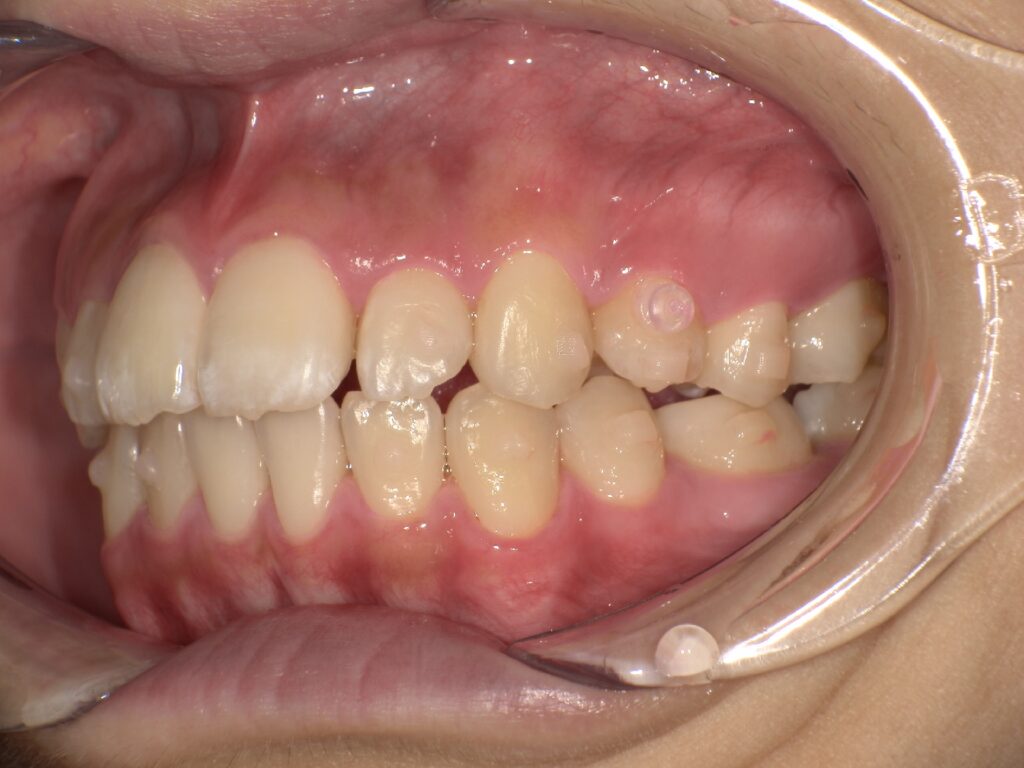

上顎の前歯が大きく突出しています

明らかに前歯の突出感が改善し、患者様はこの時点でとても喜ばれていました

矯正治療終了時 部分矯正ということもあり、短期間で矯正治療を終了することができました